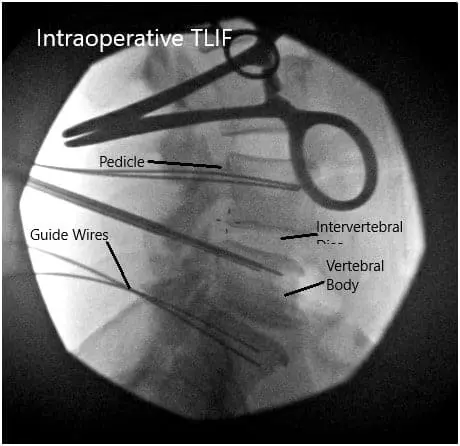

We then used blunt dissection to split the muscle fibers and palpated the edge of the transverse process.  Once we are satisfied with the positioning on the fluoroscopic imaging, we then proceeded to use a Jamshidi needle onto the lateral tips of the facet joints except for the L4 region where it was placed along the corner of the transverse process and the facet in order to avoid injuring the L3-L4 facet joint.

All needles were placed under fluoroscopic imaging and once we were satisfied with the positioning, we then evaluated his nerve monitoring and found there to be no changes within any of the needle positions.  We then proceeded to place a guidewire into the vertebral body and then removed the Jamshidi needle.

We then secured the guidewires onto the edge of the patient’s bed and turned our attention towards performing the decompression and interbody fusion procedures.  We then used a microscope to began our decompression at the L4-L5 region.

Intraoperative Fluoroscopic Images

Intraoperative Fluoroscopic Images 2

Intraoperative Fluoroscopic Images.